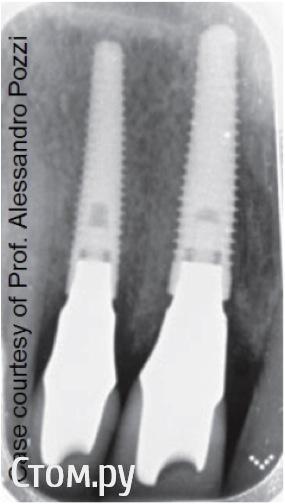

doctore Опубликовано 10 ноября, 2011 Поделиться Опубликовано 10 ноября, 2011 (изменено) ну эту картинку мы все видели ) хороший пример грамотных продаж ) Владислав, вы, как ментор Нобеля, наверняка сейчас активно начнете использовать новые имплантаты. Так вот, какая у вас будет форма абатмента на "нобель платформшифт" и "нобель ЦЦ" при установке Rp имплантата в дистальном отделе? Объем мягких тканей как раз таки легко создается десневой пластикой. Имплантолог,вероятно,крупно проигрался и задолжал.А тут две полные адентии откуда ни возьмись Согласен по поводу обьема и десневой пластики на 100%,но ведь в разумных пределах и при достаточной поддержке костной ткани(если она есть...Форма абатментов и результат,который я хочу видеть(это на Груви 4.3 и 5.0): Изменено 10 ноября, 2011 пользователем doctore Ссылка на комментарий

pit Опубликовано 11 ноября, 2011 Поделиться Опубликовано 11 ноября, 2011 (изменено) Имплантолог,вероятно,крупно проигрался и задолжал.А тут две полные адентии откуда ни возьмись Согласен по поводу обьема и десневой пластики на 100%,но ведь в разумных пределах и при достаточной поддержке костной ткани(если она есть...Форма абатментов и результат,который я хочу видеть(это на Груви 4.3 и 5.0): А Вы автор? И...... http://s42.radikal.ru/i096/1111/07/d9ba12a2a573.jpg Изменено 11 ноября, 2011 пользователем pit Ссылка на комментарий

doctore Опубликовано 11 ноября, 2011 Поделиться Опубликовано 11 ноября, 2011 (изменено) А Вы автор? И...... Пациентка одна-стороны разные.И хирургия и ортопедия мои. Изменено 11 ноября, 2011 пользователем doctore Ссылка на комментарий